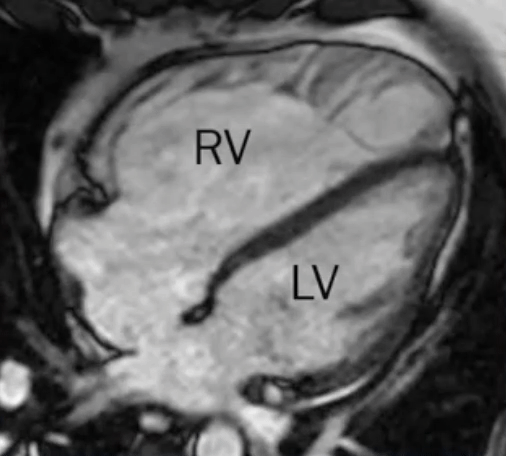

- MRI